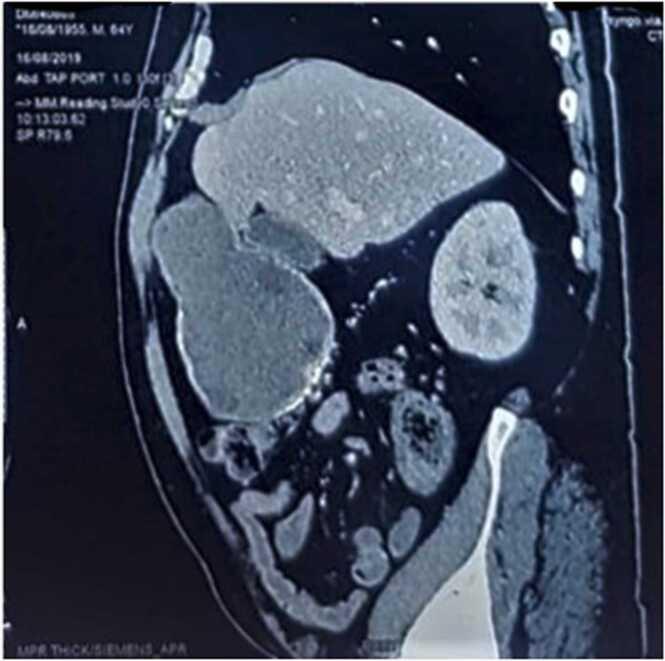

Echinococcosis is endemic in Mediterranean countries. Liver then lungs are the most affected organs. Gallbladder hydatid cyst is an exceptional localization. A 64-year-old patient was referred to our surgical outpatient department by his physician for suspicion of liver hydatid cyst based on right upper quadrant abdominal pain, associated with nausea. Physical examination showed mild tenderness of the right upper quadrant of the abdomen. A computed tomography abdominal scan showed a multivesicular cystic lesion of the segment IV measuring 9.5 × 7.5 × 13 cm with exophytic component abutting the gallbladder. The patient underwent right subcostal laparotomy. The exploration has found that the hydatid cyst is developed from the fundus of the gallbladder, without any connections or fistulas to nearby organs. A cholecystectomy was performed. Histopathological examination confirmed the diagnosis of gallbladder echinococcosis. Primary gallbladder hydatid cysts (PGHC) is an extremely rare condition, occurring in less than 0.4% of echinococcosis localizations. After literature research of case reports, only twenty-three such cases, including our case, have been reported in English literature. Due to its uncommon nature, radiologists rarely consider a PHGB as the first diagnosis. Preoperative diagnosis of hydatid cyst was possible only in 50% of cases. Therefore, a careful attention is necessary to assist in making the diagnosis preoperatively, leading to the appropriate treatment.

包虫病在地中海国家呈地方性流行。肝脏和肺是最常受累的器官。胆囊包虫囊肿是一种罕见的发病部位。一名64岁患者因右上腹腹痛伴恶心,被其医生转诊至我们的外科门诊,怀疑患有肝包虫囊肿。体格检查发现右上腹轻度压痛。腹部计算机断层扫描显示IV段有一个多房性囊性病变,大小为9.5×7.5×13厘米,有外生性成分紧邻胆囊。患者接受了右肋缘下剖腹手术。探查发现包虫囊肿起源于胆囊底部,与附近器官无任何连接或瘘管。进行了胆囊切除术。组织病理学检查证实了胆囊包虫病的诊断。原发性胆囊包虫囊肿(PGHC)是一种极为罕见的疾病,在包虫病发病部位中所占比例不到0.4%。在对病例报告进行文献研究后,英文文献中仅报道了包括我们的病例在内的23例此类病例。由于其不常见的性质,放射科医生很少将原发性胆囊包虫囊肿作为首要诊断。术前仅50%的病例能够诊断出包虫囊肿。因此,术前需要仔细关注以协助做出诊断,从而进行适当的治疗。